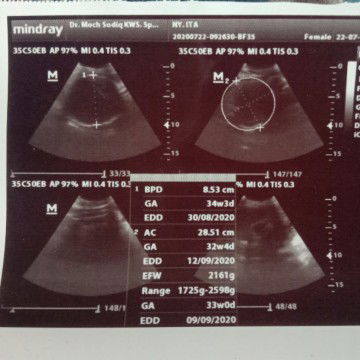

Ibu hamil

hpl 27 agst

Bun kata dokter jkel bby nya cowo tp disini kok tulisan di usg nya female ya? Bukannya female itu cewek?